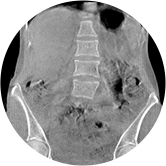

腰椎